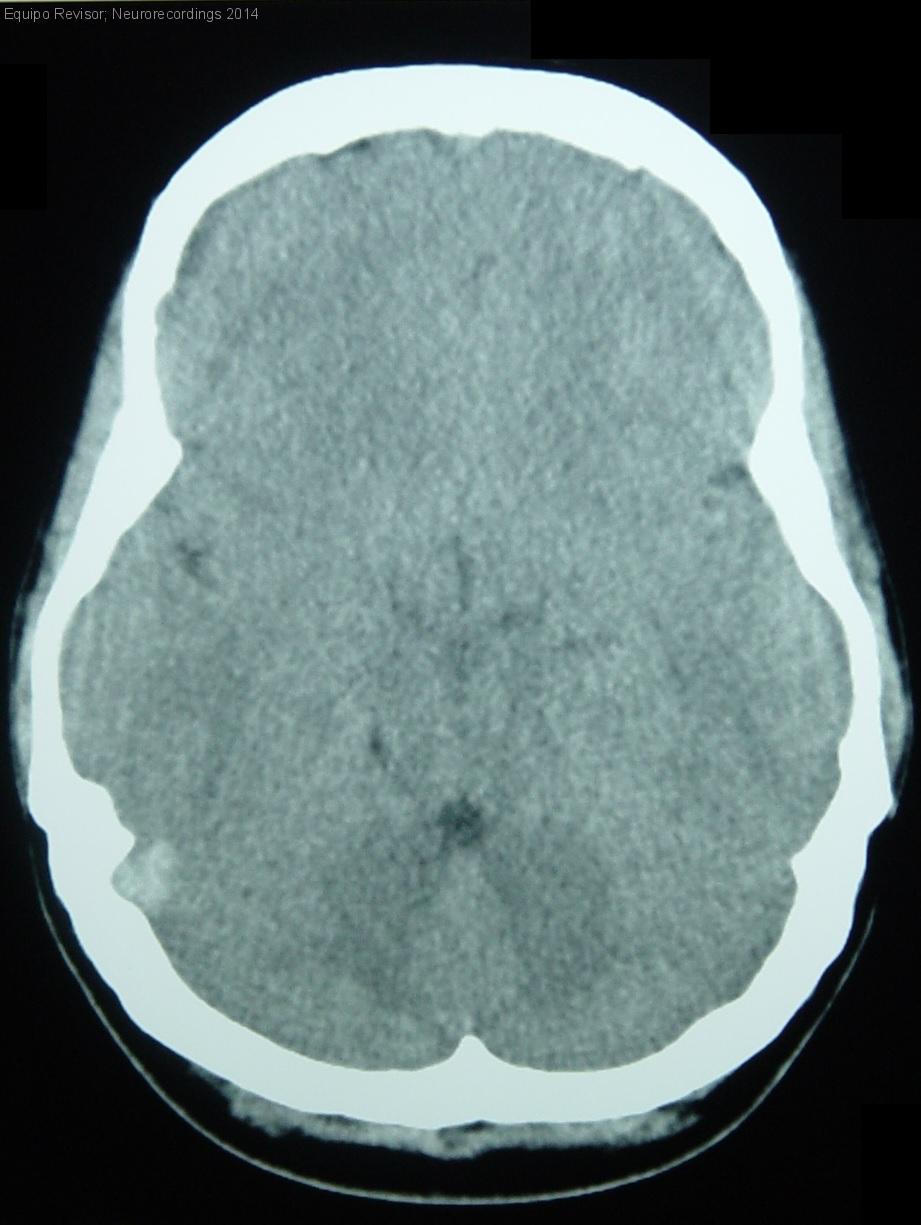

Mujer | 27 años

Diagnóstico final: Trombosis de senos venosos cerebrales

Neurología: Patología cerebrovascular | Cefalea

Etiología: Ictus